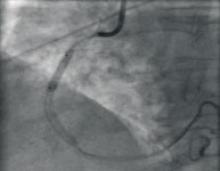

Canada is spearheading an international study to determine if an implantable cardioverter defibrillator (ICD) can prevent death from serious heart rhythm problems in those patients who’ve survived a heart attack. Heart disease is a leading cause of death in Canada and the fastest growing disease worldwide.